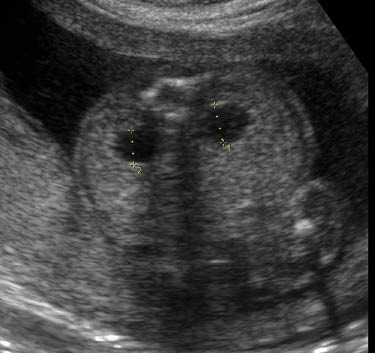

Renal pyelectasis

Dilatation of the renal pelvis is a common finding with an incidence reported to be between 0.3 and 4.5%. It is more common in male fetuses, and is often bilateral; however, if it is unilateral it is more likely to present on the left side. Although laterality does not seem to useful as a prognositic indicator, according to one study unilateral pylectasis is associated with a higher rate of urinary tract abnormalities at birth [23].

Mild pyelectasis refers to dilatation of the renal pelvis >4–5 mm and <10 mm in the antero-posterior diameter measured in transverse section of the fetal abdomen. The cut-off value which is most frequently used in this dimesion is >4 mm in the 2nd trimester and >7 mm thereafter [23].

The relation of mild pylectasis and aneuploidy, mainly trisomy 21, was first suggested by Benacerraf et al. in 1990 [23]. Others studies have subsequently supported this finding, however, all studies were done on high-risk populations [23]. Additionaly, a large multicenter prospective observational study of unselected fetuses between 16 and 26 weeks found that its association was strongest in the presence of other anomalies [24].

Examining cases of isolated mild pylectasis has found that there is very little association with aneuploidy. In a retrospective study of 25,582 low-risk pregnancies, 301 cases of isolated pyelectasis (>5 mm) were detected and none had aneuploidy [25]. In another study, Coplen and Jeanty studied 12,672 cases of which 2.9% had mild pyelectasis (>4 mm). Eight-three percent of these were isolated, and a likelihood ratio for T21 was 3.79 [26]. They concluded that in the absence of other findings, isolated pyelectasis is not a justification for amniocentesis. Lastly, another study of isolated pyelectasis was found to have a sensitivity of 0.02 for diagnosing fetuses with Down syndrome. In that case it would be necessary to screen 30,404 women in order to find one case of Down’s [27].